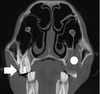

Figure 29-31. Computed tomography image of a horse that recently had 209 extracted after a midline infundibular caries-related fracture and left-sided sinusitis developed. The empty alveolus is granulating well (white circle). To prevent a similar contralateral problem, a carious infundibulum in 109 has been restored (arrow). Although the apical aspect of the infundibulum has a filling defect, this restoration is anticipated to prevent fracture/apical infection for at least 5 years.